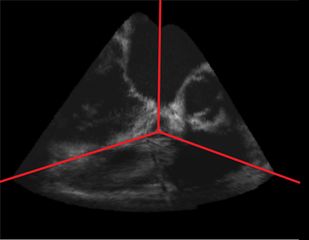

Example imaging of a porcine heart using gated 4D US reconstruction, at 50% R-R interval Danielle Pace and Terry Peters, Robarts Research Institute and The University of Western Ontario.